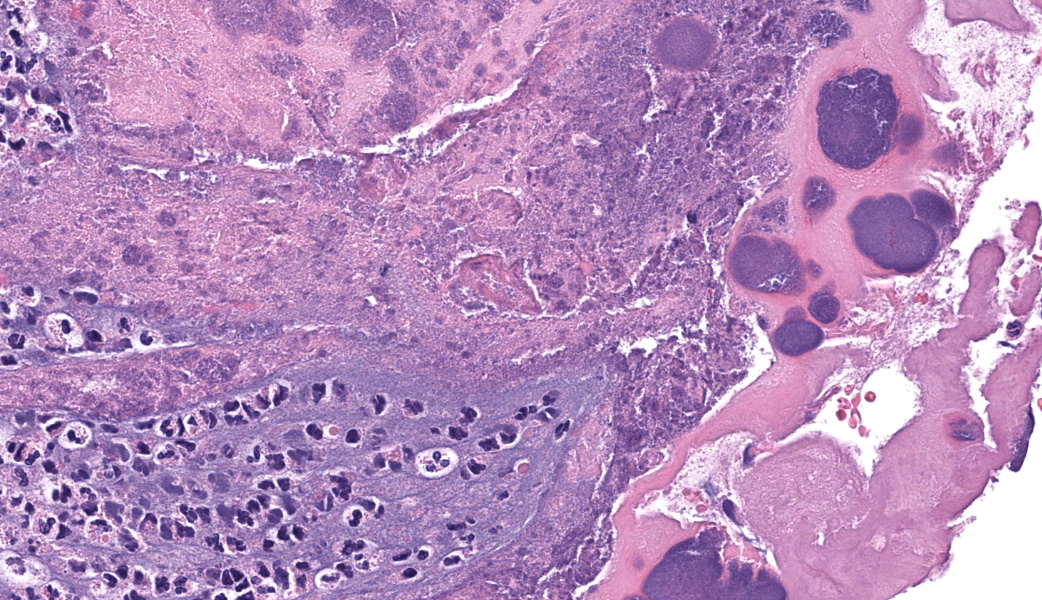

Representative sections of heart and lungs are examined.In the heart, the right atrioventricular valve is extensively overlain by large mats of fibrin, admixed with numerous degenerate and viable neutrophils and multiple coccobacilli bacterial colonies. The valvular stroma is diffusely expanded by moderate myxedema and there are moderate numbers of neutrophils and lesser numbers of hemosiderin-laden macrophages, plasma cells and lymphocytes scattered throughout the valvular stroma and expanding the endocardium of the adjacent papillary muscles. The epicardium and surrounding adipose tissue are mildly infiltrated by small numbers of neutrophils, lymphocytes, and plasma cells.

Regionally, sharply demarcated areas of the pulmonary parenchyma are markedly necrotic and replaced by abundant hemorrhage, fibrin, inflammatory infiltrates composed mainly of neutrophils and macrophages, and necrotic cellular debris. In these areas, multiple blood vessels contain thrombi consisting of large numbers of degenerate neutrophils, organizing fibrin, occasional colonies of bacterial coccobacilli, and necrotic cellular debris that variably obscure the lumen and vessel walls. Affected vessels often have smudgy, hypereosinophilic walls that are transmurally infiltrated by neutrophils, lymphocytes, and macrophages. In less affected regions, the alveolar spaces contain a small amount of fibrin, numerous foamy alveolar macrophages (some of which contain brown granular hemosiderin pigment), and fewer neutrophils and erythrocytes. There are moderate numbers of hemosiderin-laden macrophages mostly concentrated around pulmonary arteries, multifocally. Regionally, along the pleural surface there is a large amount of fibrin admixed with numerous degenerate neutrophils and necrotic cellular debris. The pleura itself is mildly thickened by fibrous connective tissue and edema and is multifocally lined by markedly reactive mesothelium, characterized by plump, rounded mesothelial cells.

Heart, right atrioventricular valve: Marked, chronic, fibrinosuppurative valvular endocarditis with intralesional bacterial colonies; Mild, multifocal, suppurative epicarditisLungs: Marked, regional, suppurative, necrotizing embolic pneumonia with vascular thrombosis and intrathrombotic bacteria; Marked, regional, fibrinosuppurative pleuritis

1. Heart, right AV valve: Valvulitis, fibrinosuppurative, chronic, focally extensive, severe, with valvular remodeling and numerous colonies of coccobacilli.

2. Lung: Pneumonia, embolic, necrotizing and suppurative, chronic, multifocal to coalescing, severe, with septic arterial thrombi and suppurative pleuritis.